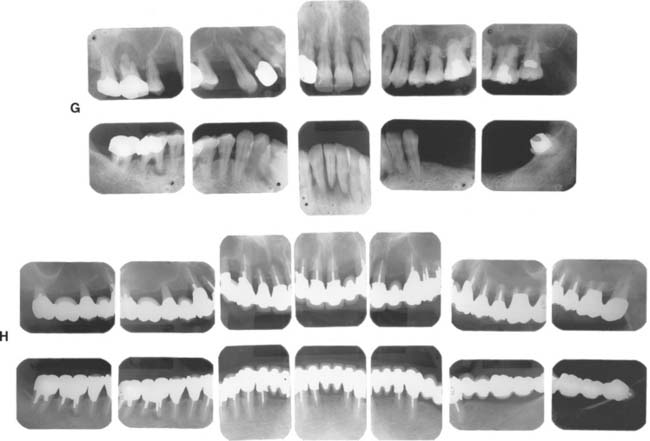

Fig. 32-43 Long-term follow-up after comprehensive treatment with fixed prostheses of the patient in Fig. 32-41 (Treatment XI). A to E, Preoperative photographs. F to J, Postoperative photographs. K, Preoperative radiographs. L, Fourteen-year postoperative radiographs. If the fixed prostheses have been designed carefully and the patient is cooperative and maintains excellent plaque control, fixed dental prostheses can withstand the test of time. Today, these prostheses continue to provide excellent esthetics and function after more than 16 years of service. Note that no intervention was done for the impacted canine. Initially, this patient presented with only posterior guidance on the left and right first molars. A gingival graft was performed on the left side before the fixed prosthodontic treatment. Fourteen years later, all teeth are stable without any clinically significant mobility, and the anterior guidance components exhibit no visible faceting. No significant change has occurred in bone levels, whereas apparent radiographic bone densities appear slightly increased. Meticulous attention to precise adjustment of the occlusion, especially the anterior guidance component, contributed to the long-term success of this treatment. On the 14-year postoperative radiographs, no signs of occlusal trauma are seen. Also, note that three endodontically treated molars have very large access cavities. Such teeth have a guarded prognosis and are prone to fracture, but no fractures have occurred. Again, this suggests the importance of precise and optimal load distribution at the time of initial treatment and during periodic follow-up appointments. This patient was recalled every 6 months.